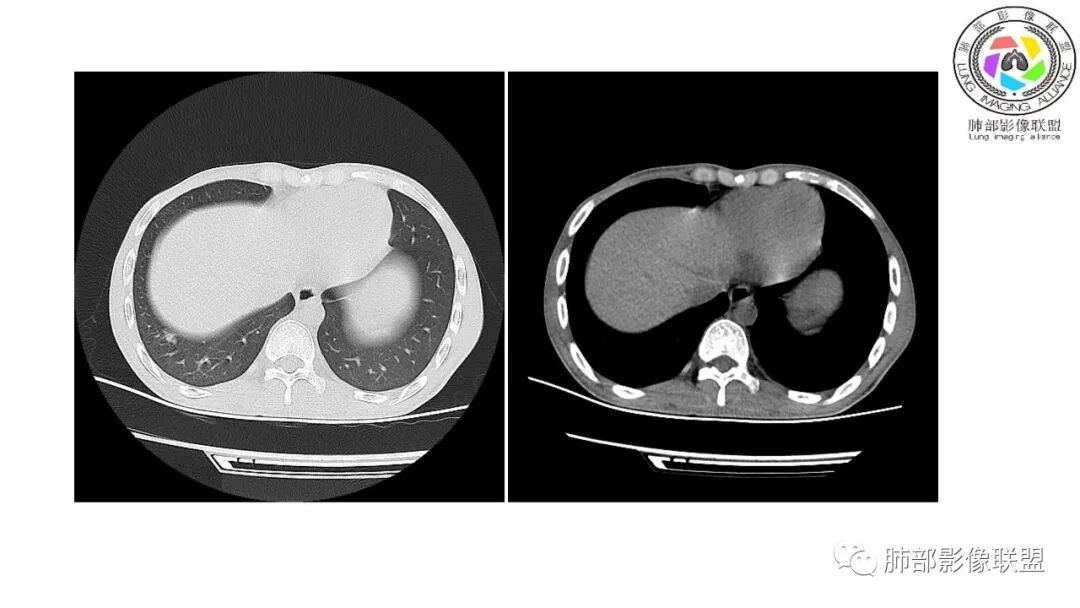

影像与临床:1.青年男性,HlV阳性,颜面部皮疹(未提供皮疹图像)、发热(高热),实验室CRP、PCT高,T-Spot阴性。2.右肺下叶空洞结节,壁厚不均,边界清楚,其内线状影,未见液平及钙化,未见卫星灶,纵隔淋巴结增大,双侧腋窝见增大淋巴结。心腔内低密度提示贫血可能。肝脾影增大,未见结节影及块影。腹膜后见多发增大淋巴结。

综合分析:本例肺部影像学改变并不具有特征性,空洞性病灶须与多种疾病鉴别,但年轻HIV阳性患者,高热,皮疹,肝脾增大,纵隔、腋窝、腹膜后见多发增大淋巴结等都强烈提示马尔尼菲篮状菌感染的可能性。

南边:12日好一些

南边:支持炎性,结合病史,马尼首选